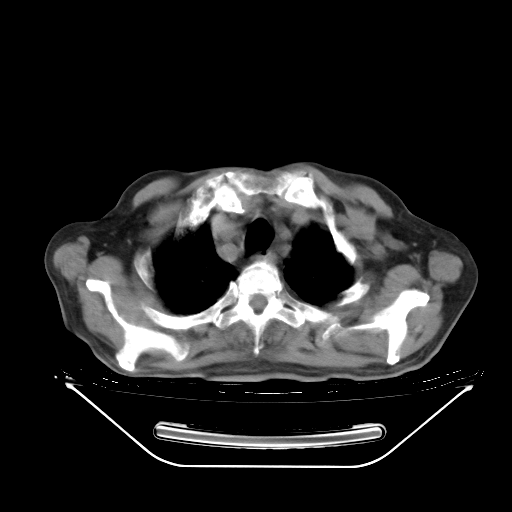

今天复查肺部CT,发现双肺广泛磨玻璃样改变。所以我把3月19日和5月9日相隔50天的肺部CT上传。请大家会诊。

2009年3月19日肺部CT片。

2009年3月19日肺部CT